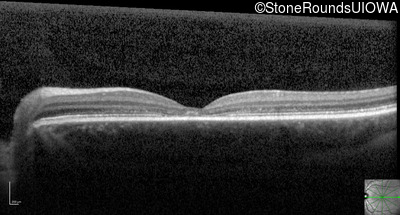

Optical Coherence Tomography - Right - 20/32

Exemplar / OCT Stack